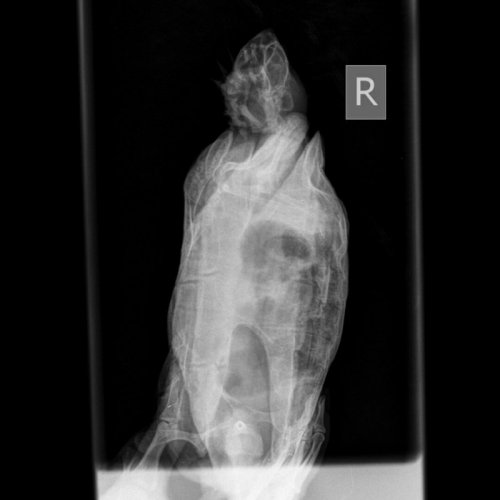

Podolnyi Ваше имя: Подольный Константин Локация: Украина, Днепр Опубликовано: 27 июня 2020 Опубликовано: 27 июня 2020 @_Pineapple_ рентген есть возможность сделать ? Вентродорсальная и правая латеральная

_Pineapple_ Ваше имя: Лежнина Анастасия Локация: Россия Томск Опубликовано: 1 июля 2020 Автор Опубликовано: 1 июля 2020 @Podolnyi Здравствуйте. Черепаха теперь спокойно погружается и даже съела кусок мяса, который я ей предложила (небольшой, я просто проверяла, станет ли есть). Сделали рентген.

Podolnyi Ваше имя: Подольный Константин Локация: Украина, Днепр Опубликовано: 2 июля 2020 Опубликовано: 2 июля 2020 У черепахи выраженный метеоризм (вздутие) жкт. Кальций начать снова будет, через неделю от сегодняшнего дня, по той же схеме. заставлять ее двигаться и делайте вибротерапию по 30 минут 2 раза в день. Яиц и фолликулов я не наблюдаю, но это не означает, что нет последних.